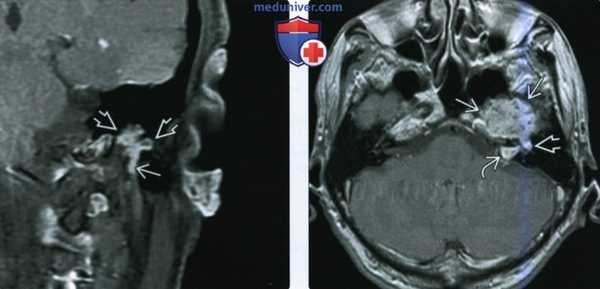

При проведении МРТ головного мозга пациентки В. на 3-и сутки после операции выявлена остаточная часть опухоли в канале подъязычного нерва (рис. 5). Рис. 5. МРТ головного мозга пациентки В. на 3-и сутки после операции. При усилении сигнала парамагнетиком определяется остаток опухоли в канале подъязычного нерва справа (указано стрелкой).

(Слева) При аксиальной КТ в костной окне определяется объемное образование в расширенной ямке коленчатого ганглия с распространением опухоли вдоль переднего барабанного сегмента ЧН VII со смещением слуховых косточек латерально. Наружная поверхность слуховой капсулы истончена ШЛН.

(Справа) При аксиальной МРТ Т1 С+ FS у этого же пациента визуализируется контрастирующаяся ШЛН, расположенная в коленчатом ганглии. Опухоль распространяется вдоль барабанного сегмента ЧН VII и во внутренний слуховой канал по лабиринтному сегменту ЧН VII. Обратите внимание на интрамуральную кисту медиально.